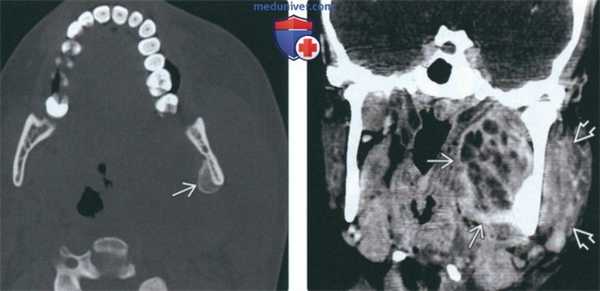

(Слева) На аксиальной КТ в костном окне у этого же пациента определяется периостальная реакция, характерная для остеомиелита нижней челюсти.

(Справа) На корональной КТ с КУ у этого же пациента определяется многокамерный абсцесс внутреннего жевательного пространства в сочетании с отеком и утолщением жевательной мышцы в наружном жевательном пространстве.

(Слева) КТ в коаном окне в аксиальной проекции у этой же пациентки. Формирование новой костной ткани в области надкостницы говорит о наличии остеомиелита нижней челюсти.

(Справа) При КТ с КУ в коронарной проекции у этой же пациентки в медиальных отделах жевательного проаранава определяется многокамерный абсцесс. В латеральном жевательном пространстве визуализируется увеличенная и отечная жевательная мышца.